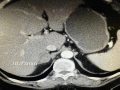

右侧肾上腺肿瘤

大小30mm